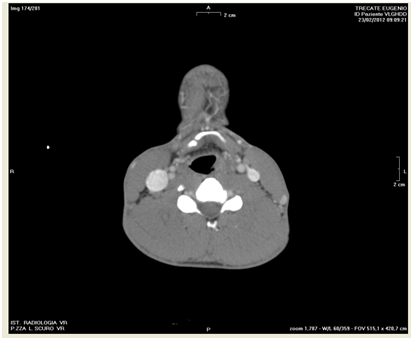

A 39year-old man was struck by a barbell at the cervico-facial junction while exercising at gym. He was referred to our ENT department after a assessment in the Emergency Department. The patient was alert and cooperative and his presenting symptoms were dysphonia, neck pain, odynophagia and dysphagia. He did not complain of shortness of breath, cough or gagging. Examination of the neck did not reveal swelling or surgical emphysema. He underwent flexible nasolaryngoscopy which showed significant swelling of the left side of larynx (left arytenoid, left aryepiglottic fold and left piriform recess). The mobility of the left vocal fold was impaired however there were no signs of compromise of the supra-glottic airway nor injury of the hypo pharynx nor bleeding. A Computerized Tomography with contrast showed isolated fracture of the hyoid bone in the right para-median region (Figure 1) and oedema of the left larynx (Figure 2).

Figure 2 Oedema of the left larynx.